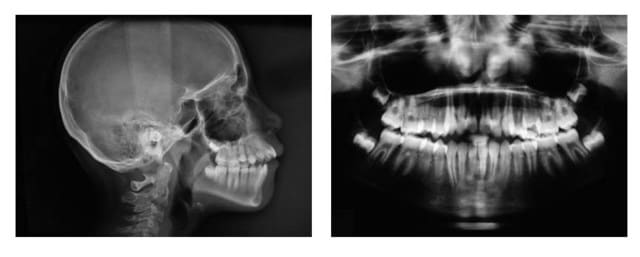

voici un cas de gencive fine et os semblable

Rx 1 gi6zec - Eugenol

Depart abma1m - Eugenol

situation actuelle

avec l’accord des parents, qui ont été prévenus que le ttt. pouvait être interrompu pour raisons parodontales, j’ai commencé le ttt. en repoussant la greffe à la fin du ttt. si pas de Pbs.

@+ Bjc.

Actuel viclc9 - Eugenol